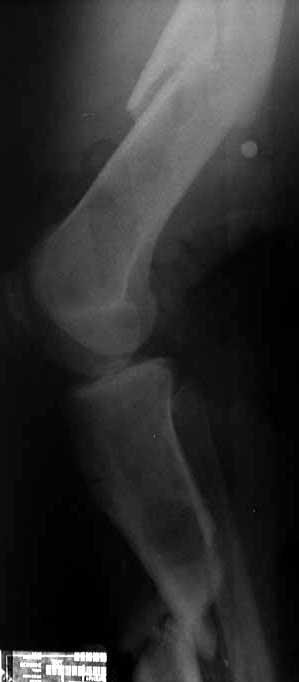

Here is a close up of the regenerate under hot light. There is a small amount of wispy regenerate. Would you continue advancing? Ive placed a bone stim over the regen site. Most likey will convert to nail.

JN> Here is a close up of the regenerate under hot light. There is a small amount of wispy regenerate. Would you continue advancing?

Expected time of maturation looks too long so in case of ex-fix as definitive stabilization i would prefer to drop distraction back and re-do corticotomy higher, at the middle of the segmental fragment.

JN> Ive placed a bone stim over the regen site. Most likey will convert to nail.

It seems to me there is high risk to go to the situation you started from, just with the gap located at another place. Intuitively, probability to have the defect healed before the nail gets broken looks less than acceptable. Maybe thick nail with thick screws would resist long enough. Also bone grafting of the distal defect can be presumed in case of poor bone formation revealed in 3-4 months after conversion.